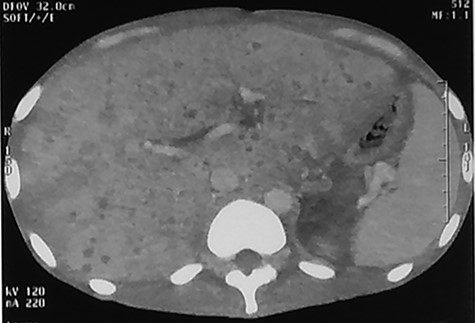

The post-operative status was marked by the persistence of SIRS, a deterioration of general appearance, pain in the right hypochondrium and hepatomegaly noticed on the eighth post-operative day. No jaundice was noted. A contrast-enhanced abdominal CT scan was performed showing small, homogeneous hypodensities disseminated in the liver parenchyma giving the appearance of miliary abscess. There was no lymphadenopathy or associated ascites (Fig. 1).

Abdominal CT injected at portal phase performed on 10th postoperative day showing millimetric, homogeneous hypodensities disseminated in the hepatic parenchyma.